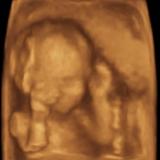

Ciao a tutte, volevo sapere se a qualcuna é capitata la mia stessa situazione. L’iter della gravidanza in sintesi é andato così: ecografie nel primo trimestre fatte dalla mia ginecoga che ha effettuato poche misurazioni senza mai rilasciarmi null’altro che 2/3 foto delle eco e dubbio sulla datazione di 1 settimana circa, prima ecografia ufficiale con misurazioni quella della amniocentesi dove si conferma la datazione da ultima mestruazione e quindi dpp 3/3/2018, eco morfologica 2° trimestre dove invece si accorgono che é indietro di 8 GG così ridatazione e dpp all’11/3/2018, eco 3° trimestre indietro ancora di 5 GG ma tutto OK e rimaniamo con dpp 11/3, ultima eco dalla mia ginecologa a 33+4 dove misura e mi dice che va tutto bene in linea con le settimane di gestazione. Settimana scorsa vado in ospedale x fare ultimi esami e cartella clinica e mi spiegano che le ridatazioni vanno fatte nel primo trimestre quindi per loro la dpp esatta é il 3/3 e visto che la bimba é alla 39° settimana ma risulta indietro di 18 gg per un peso di 2,800 kg mi hanno inserito nel programma IUGR anche se in realtà tutte le misure sono intorno al 25° percentile se si considera dpp il 3/3 e poco sotto al 50° se si considera l’11/3.